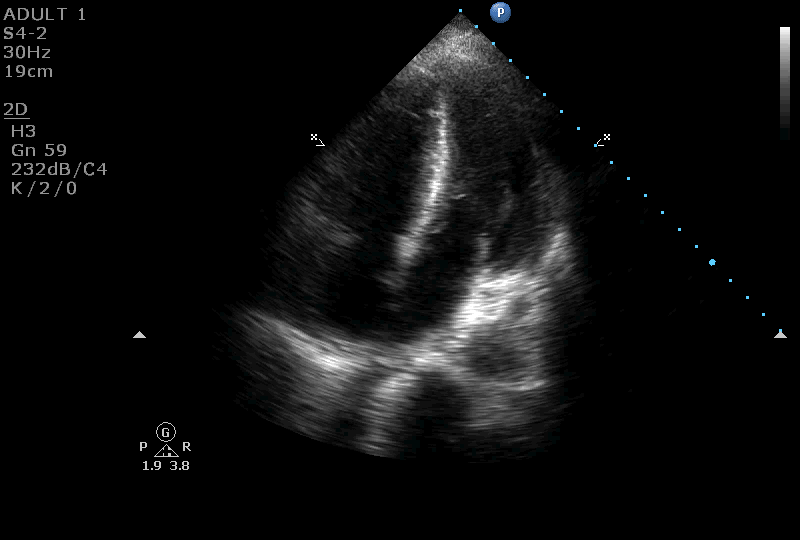

On further evaluation, the patient’s echocardiogram showed a 4.5 x 4.3 cm cystic tumor in the right atrium, hypertrophied obstructive cardiomyopathy with moderate left ventricular outflow tract obstruction, and good left ventricular function. She also underwent computed tomography (CT) and magnetic resonance imaging (MRI) of the chest, which revealed a neoplastic mass lesion, most likely right atrial myxoma.